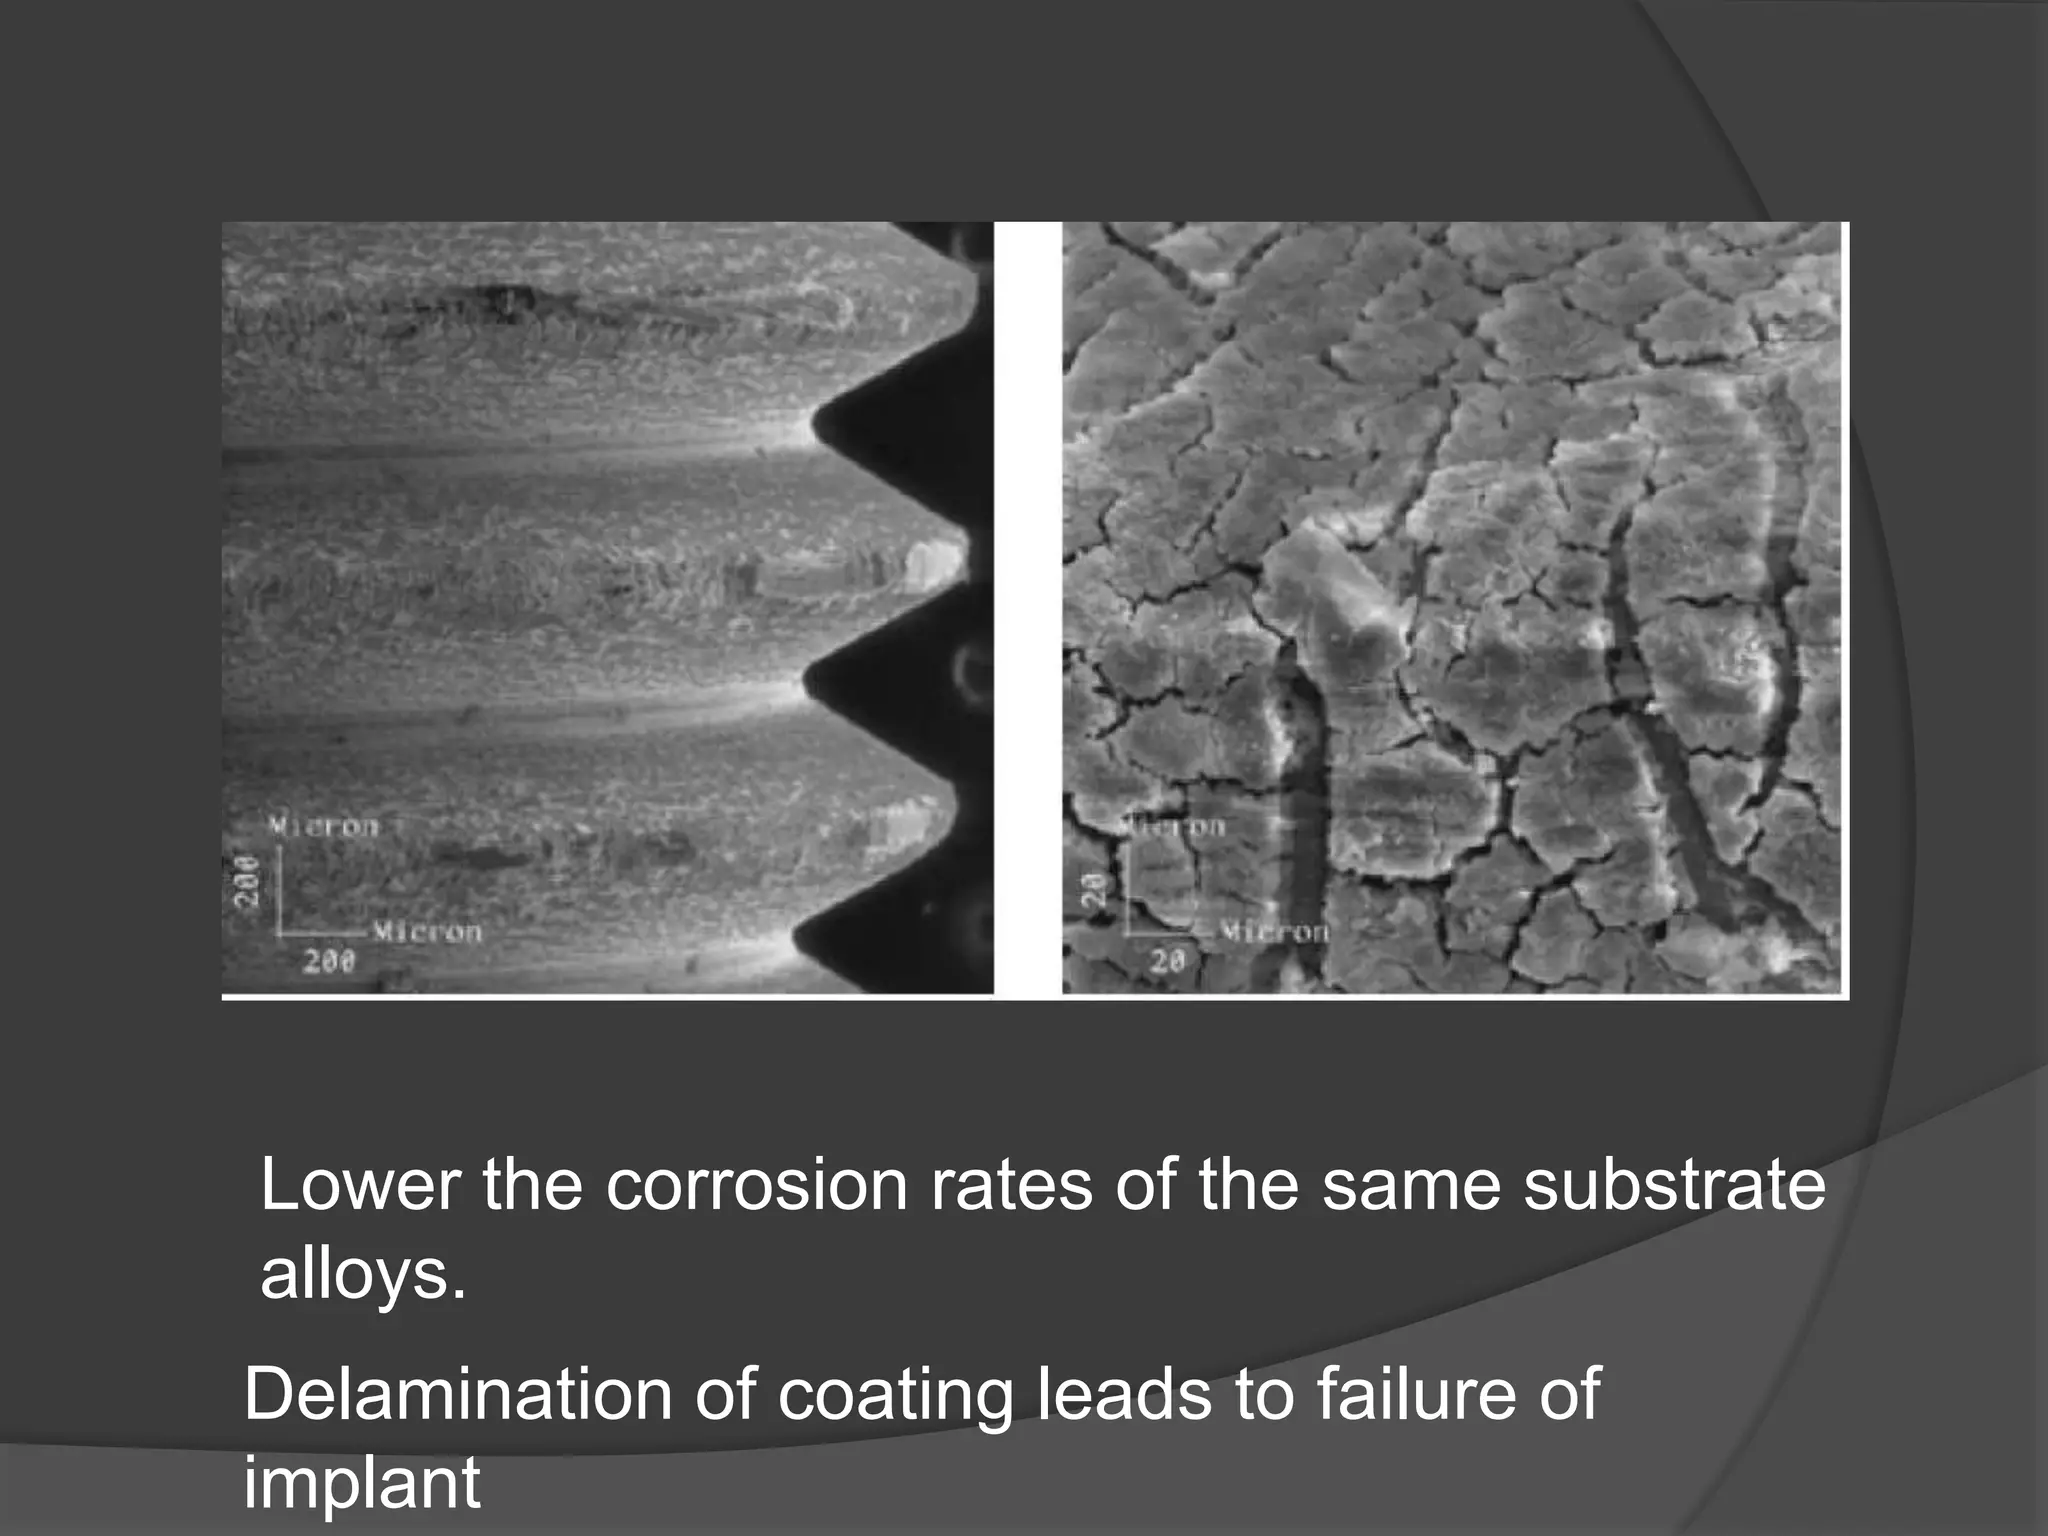

This document discusses factors that influence osseointegration and primary stability of dental implants, including implant design characteristics, surgical technique, and loading protocols. Specifically, it covers the processes of osseointegration and how forces on implants can either promote or inhibit bone remodeling. Key implant design considerations like length, diameter, threads, coatings and surface topography are analyzed in terms of their effects on stress distribution and bone-implant contact. The importance of primary stability and factors influencing it like bone quality and surgical skill are also addressed. Loading protocols ranging from immediate to conventional loading are compared.